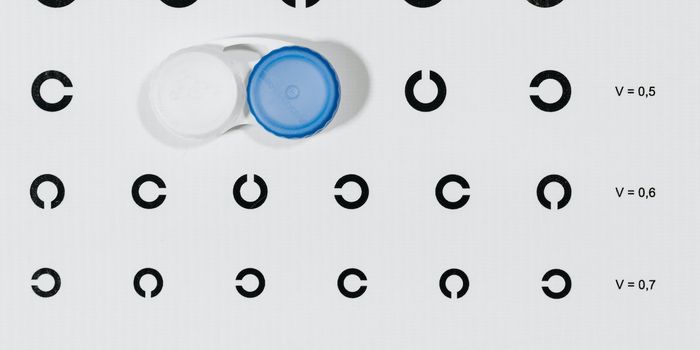

AUG 30, 2024Cannabis SciencesA study published in Ophthalmic and Physiological Optics examined the connections between John Lennon’s myopia, co ...

AUG 22, 2024Space & AstronomyHow does spaceflight affect vision loss in astronauts for both the short and long term? This is what a combined effort b ...